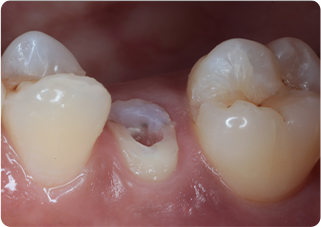

精密根管治療③

術前

術後

| 主訴 | 奥歯で噛むと痛い |

|---|---|

| 治療期間/回数 | 1ヵ月、4回 |

| 価格(税込) | 88,000円(税込) |

| リスク・副作用 | 病変再発、歯根破折の可能性 |

| ポイント | う蝕検知液を用い、むし歯の取り残しが無いようにし、ラバーダム防湿を行い、無菌的に根管治療を行った。根管充填材は、殺菌作用の強い保険適応外のMTAセメントを使用した。 |